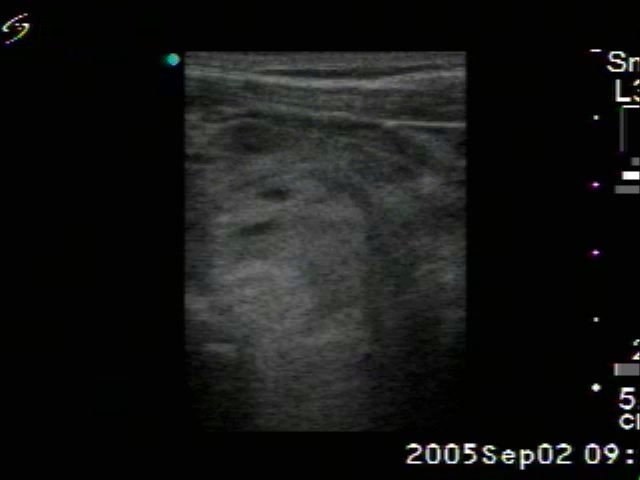

Benign nodular hyperplasia - Case 33. |

Clinical presentation: a 76-year-old man with hoarseness. The goiter was known for decades and grown slowly. Laryngology revealed palsy of the left nervus recurrens.

Palpation: both lobes of the thyroid were highly enlarged and nodular.

Ultrasonography: a multinodular goiter with both retrotracheal and substernal spread.